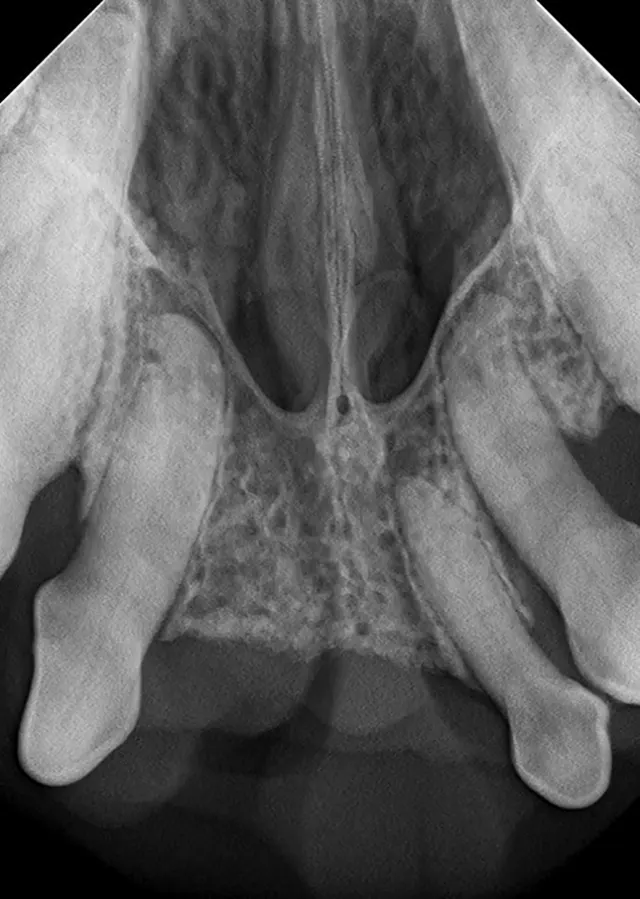

The relatively simple parallel technique is used to image the mandibular caudal cheek teeth on small dogs and cats.

For large dogs, use this technique to image teeth from the third premolar to the last molar. This portion of the oral cavity has room enough to place the sensor parallel and adjacent to the desired teeth, on the lingual aspect of the mandible. Then, aim the tube head perpendicular to the sensor.

This technique, which is used to image the rostral mandible and entire maxilla, is the only technique that produces an image without distortion when done correctly. Some technicians find the bisecting angle technique difficult to grasp; however, it can be simplified with proper patient and equipment positioning.

For example, image the caudal cheek teeth in the maxilla with the tube head at a 60° angle from the horizon.2 When the patient is positioned with the maxilla parallel to the horizon, the sensor can also be placed parallel to the horizon (ie, inside the oral cavity and adjacent to the desired teeth), making it much easier to visualize the angle.

Place the sensor horizontally inside the oral cavity, with the cusp tip of the desired teeth at the edge of the sensor. Placing the sensor inside the oral cavity will provide enough room to catch the radiograph image.

Radiographs should be taken in the same order each time. Starting with the right maxillary molars, move the sensor and tube head around the entire arch until the left caudal maxilla is reached. Then, position the patient in ventral recumbency and repeat the process, starting with the left mandibular molars. Continue around the arch until the right caudal mandible is reached. This sequence is suggested because full-mouth-series templates included in most digital software programs are arranged in this order and will result in the mirror image for correct viewing of radiographs.